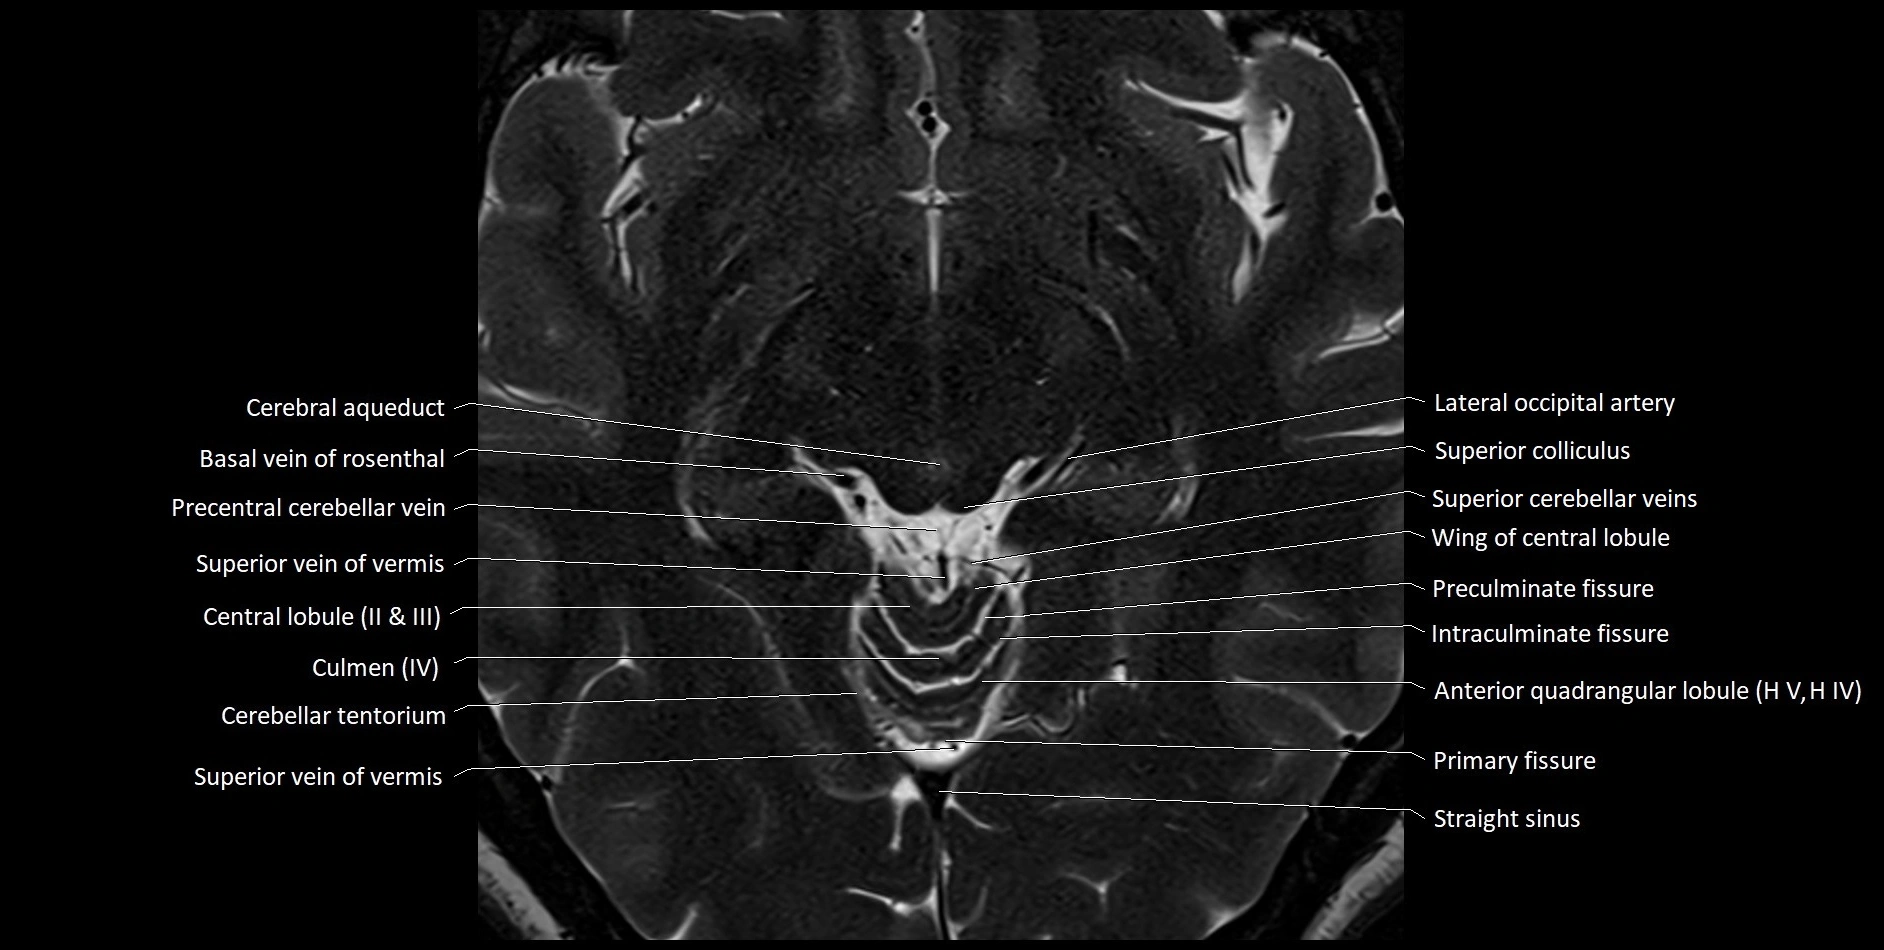

MRI images